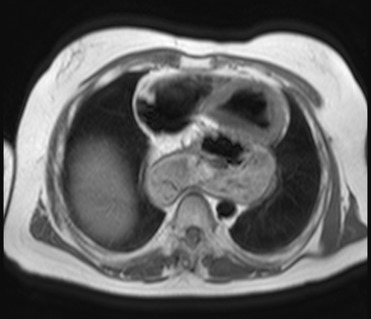

Магнитно-резонансная томография не является базовым исследованием для диагностики грыжи пищеводного отверстия диафрагмы, потому что не обеспечивает достоверного визуального контроля за динамическими изменениями положения желудка при смене положения тела и не позволяет выявить моментальное смещение абдоминальных органов в грудную полость в условиях физиологической нагрузки. Грыжа пищеводного отверстия диафрагмы представляет собой анатомическое перемещение кардиального или фундального отдела желудка через диафрагмальное отверстие, часто сопровождающееся гастроэзофагеальным рефлюксом. Базовым диагностическим исследованием является рентгеноконтрастное исследование пищевода с барием. МРТ выявляет следующие анатомические признаки:

В режиме трёхмерной реконструкции визуализируется пространственное положение грыжевого мешка относительно диафрагмы, сердца и сосудистых структур, что важно для предоперационного планирования.

В режиме трёхмерной реконструкции определяется пространственное взаимоотношение пролабированного желудка, диафрагмы и органов грудной полости.